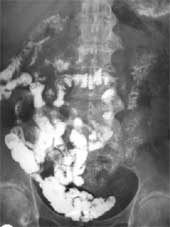

Перемеживающийся характер поступления бариевой взвеси в кишку наступает в более отдаленный послеоперационный период. Заполнение тощей кишки зависит от темпов эвакуации контрастного вещества из культи желудка и состояния анастомоза. Ускоренная эвакуация приводит к перенатяжению контрастной массой проксимальных отделов тощей кишки, просвет ее становится расширенным (Рис. 1). Пассаж бариевой взвеси по этому отрезку кишки, по мнению большинства авторов, становится ускоренным, хотя в дистальных отделах наблюдается некоторая гипомобильность. Однако бариевая взвесь достигает слепой кишки в несколько ранние временные промежутки. Нередко у этой категории оперированных наблюдается желудочнопищеводный или дуоденогастральный рефлюкс.

Рис. 1. Расширение начальных отделов тощей кишки вблизи культи желудка.